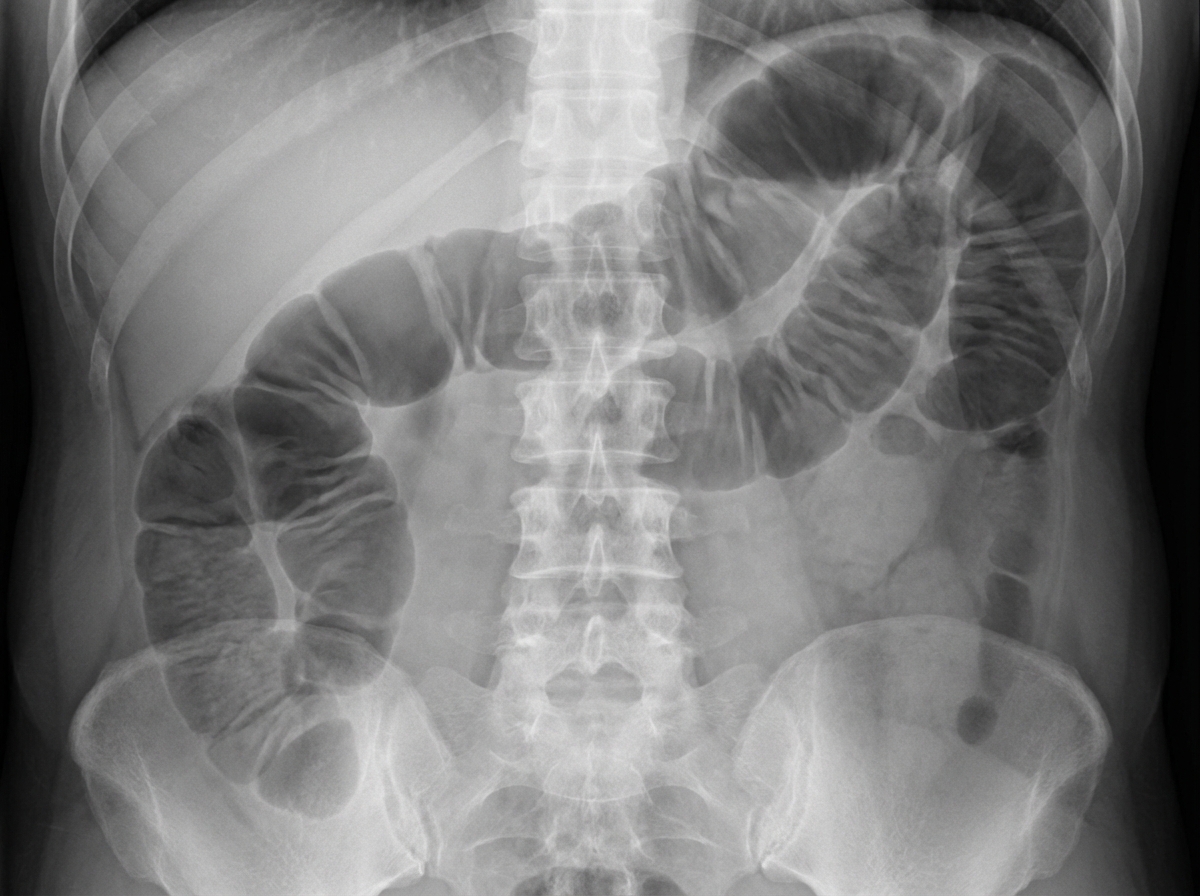

A 63-year-old man is brought to the emergency department for evaluation of abdominal pain. The pain started four days ago and is now a diffuse crampy pain with an intensity of 6/10. The patient has nausea and has vomited twice today. His last bowel movement was three days ago. He has a history of hypertension and recurrent constipation. Five years ago, he underwent emergency laparotomy for a perforated duodenal ulcer. His father died of colorectal cancer at the age of 65 years. The patient has been smoking one pack of cigarettes daily for the past 40 years. Current medications include lisinopril and lactulose. His temperature is 37.6°C (99.7°F), pulse is 89/min, and blood pressure is 120/80 mm Hg. Abdominal examination shows distention and mild tenderness to palpation. There is no guarding or rebound tenderness. The bowel sounds are high-pitched. Digital rectal examination shows no abnormalities. An x-ray of the abdomen is shown. In addition to fluid resuscitation, which of the following is the most appropriate next step in the management of this patient?